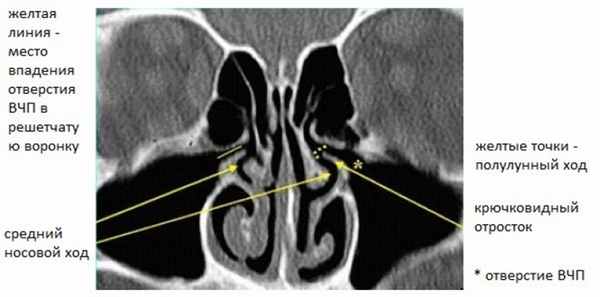

Рисунок 1. КТ полости носа. Нормальный передний остиомеатальный комплекс Хорошо видна анатомия решетчатой воронки и крючковидного отростка.

Крючковидный отросток (КО) и латеральная стенка полости носа формируют решетчатую воронку (РВ). Вышеуказанные пазухи дренируются в РВ через разные отверстия. Отверстие верхнечелюстной пазухи (ВЧП) и карман (или проток) лобной пазухи (ЛП) (см. Рис. 2) открываются в самую переднюю часть ОМК, хорошо и постоянно видны на КТ сканах.